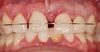

La patiente souhaite corriger son sourire mais présente des saignements gingivaux. Un incisive maxillaire est légèrement mobile.

Le cliché panoramique révèle une perte osseuse discrète.

L’examen microscopique révèle la présence de nombreuses bactéries mobiles, dont des spirochètes.

Un traitement parodontal de 10 séances sur 10 mois va permettre de stabiliser la maladie parodontale. L’évolution de la profondeur des poches parodontales est très favorable et permet le traitement orthodontique et la chirurgie orthognathique.